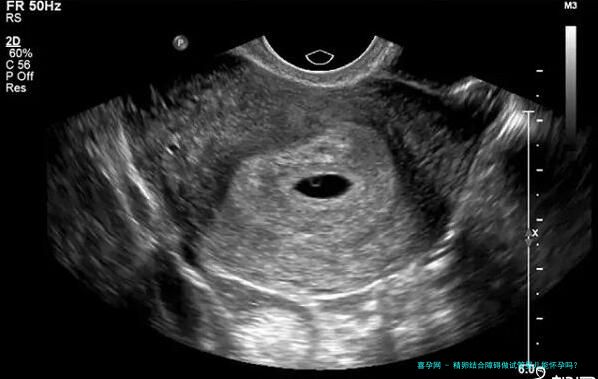

2、促排卵:通过超声引导下的穿刺手术,从卵巢从中获取出成熟的卵子。